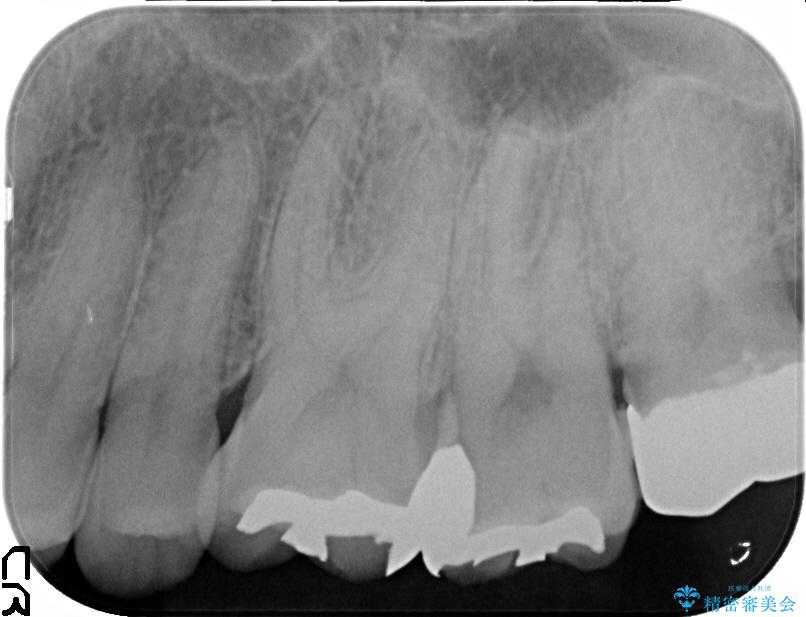

保険で治療した銀歯は、経年劣化で詰め物のふちが欠けたり、適合が悪くなり詰め物の下など目に見えない部分の虫歯の原因となることがあります。また、金属のため口にするものの熱の影響を受けやすく成分が溶けやすくなったり、変形してしまうことがあります。

セラミックスは、見た目の審美性だけでなく劣化がしにくいことや金属アレルギーのリスクがないことがメリットとしてあげられます。

ただし、セラミックスは日常の食事や歯ぎしりなどで詰め物が欠けたりする可能性があります。